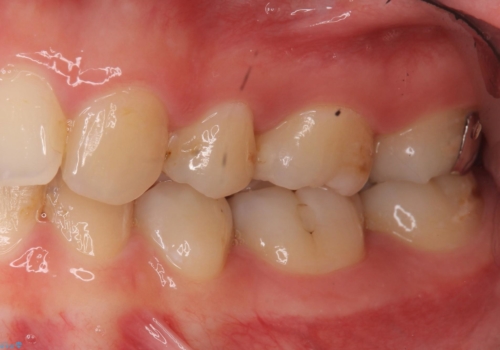

- 奥歯の歯と歯の間が虫歯になっていました。

セラミックインレーで治療しました。

虫歯が進行して、神経に近くなると、冷たいものが染みたりする神経症状が出てきます。

そういった自覚症状が出る前に処置することをおすすめします。